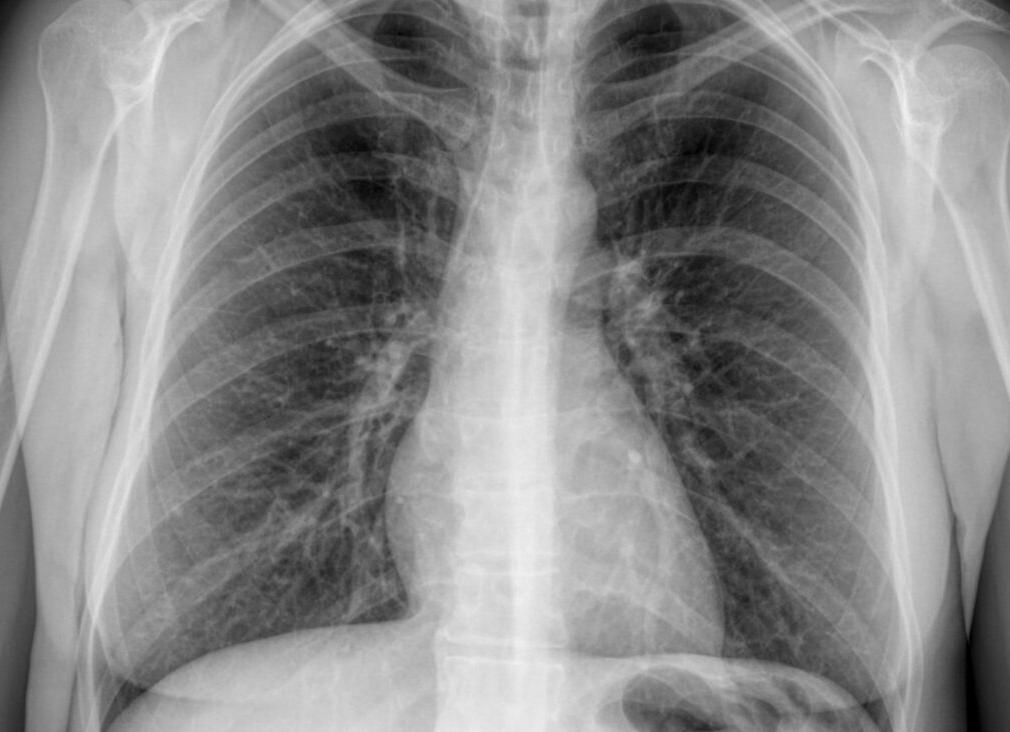

Чем отличается флюорография от рентгена легких? Флюорография — это метод рентгенологического исследования, суть которого состоит в фотографировании изображения с флюоресцентного рентгеновского экрана. Предназначена для последующей оцифровки изображений, на фотопленку определенного формата, обычно 110×110 мм, 100×100 мм или что менее желательно, 70 x 70 мм. То есть по итогу изображение всегда меньше.

Важным шагом в развитии рентгенологии как науки стало широкое использование нового метода флюорографии – цифровая. В то же время рентген также инструментальный метод исследования, но существенная разница в том, что в нем изображение выводится на пленку, и разрешительная способность этого метода выше. Уже, исходя из определения, понимаем, чем отличается рентген от флюорографии. Стоит проанализировать преимущества и недостатки каждого метода, чтобы все-таки понять, рентген и флюорография, в чем разница.

Если идти от обратного, рентген дороже, чем флюорография. Основная дороговизна из-за пленки. Но именно она дает возможность увидеть четкое и качественное изображение легочного рисунка. По информативности она в разы выше, и главный плюс этого скринингового метода – низкая лучевая нагрузка. А для каждого фтизиатра это колоссальная возможность наблюдать процессы в динамике, делая снимок приблизительно 2 — 3 раза в 6 месяцев, что является непозволительно роскошью при флюорографии. Плюс этого метода в том, что его можно применять в обследовании детей. Специфическую туберкулинодиагностику в виде пробы Манту проводят до 14 лет включительно, после чего рекомендована флюорография. Но после 5 лет, проба Манту не столь показательна, и тогда стоит выбор флюорография или рентген. К тому же на флюорографии ни один фтизиатр не увидит специфического заболевания. Этот метод является пусковым механизмом в дальнейшей диагностике. С помощью рентгенографии можно увидеть полную картину воспалительного процесса в легких, что очень помогает при дифференцировании заболеваний дыхательной системы.

После проведения обзорной или прицельной рентгенограммы получают четкое изображение рисунка легких, на котором будут видны мельчайшие патологические изменения в диаметре не более 2 мм. Рентгеноскопия эффективна как метод подтверждения и уточнения диагноза, но поскольку даже минимальное излучение цифрового рентгеновского аппарата вредно для человека, ее нужно делать только в случае реальной необходимости. В целях профилактического обследования процедуру не выполняют, но при определенных мерах безопасности его проводят детям и беременным.

Рентген органов грудной клетки информативнее флюорографии. В проекции на изображении можно обнаружить тени очагов поражений в диаметре не превышающие 2 мм, тогда как при флюорографии улавливаются изменения в диаметре не менее 5 мм.

Снимок может быть получен на фотопленке или в цифровом виде, однако, первый способ в наши дни уже считается устаревшим. В случае рентгенологического обследования делается фотоснимок конкретного внутреннего органа грудной клетки. Рентген органов грудной клетки позволяет получить прямую проекцию органа, в то время, как при флюорографическом обследовании на снимке видна только тень от внутреннего органа. Четкость изображения конкретного объекта в первом случае получается намного выше, чем во втором, однако при цифровой флюорографии легких пациент получает существенно меньшую дозу радиационного облучения.